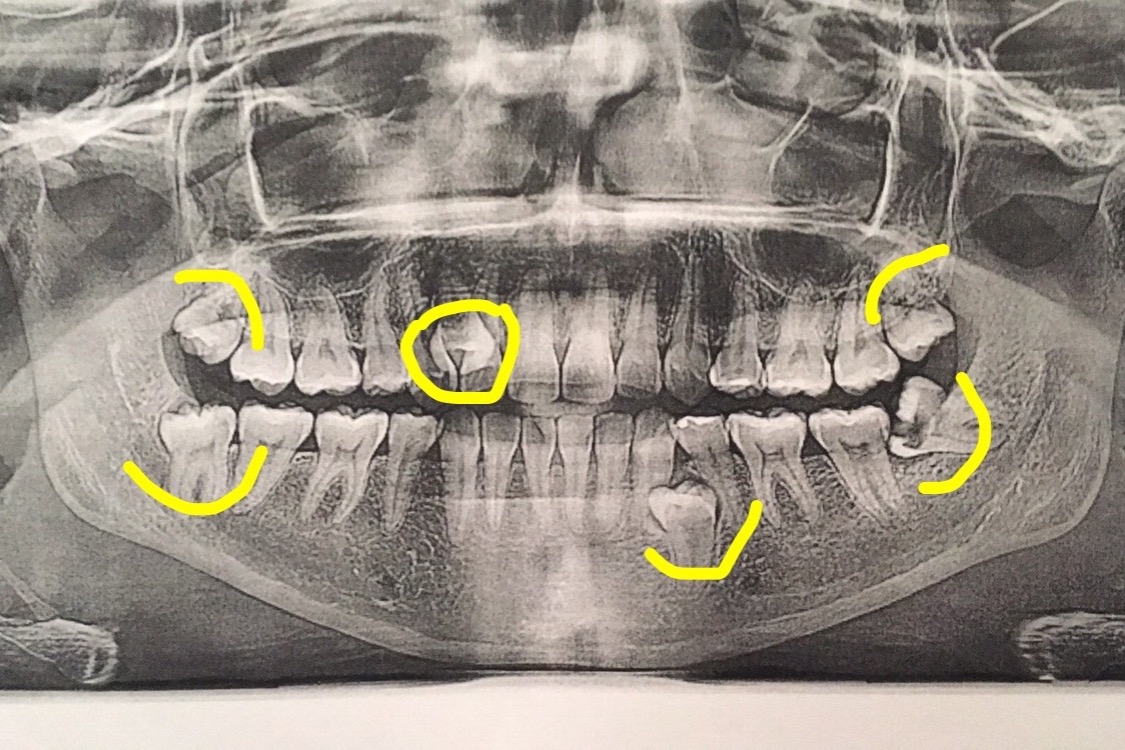

I have 4 wisdom teeth coming, one of them coming in completely sideways that now has a hole in it, and is close to hitting my jaw bone that needs to be out urgently. It has been causing pain, fogginess, and migraines.

In addition to that, I have 2 extra (supenumerary) teeth, one that is already out, and the other on the same side as the impacted wisdom tooth, creating pain and discomfort as well.